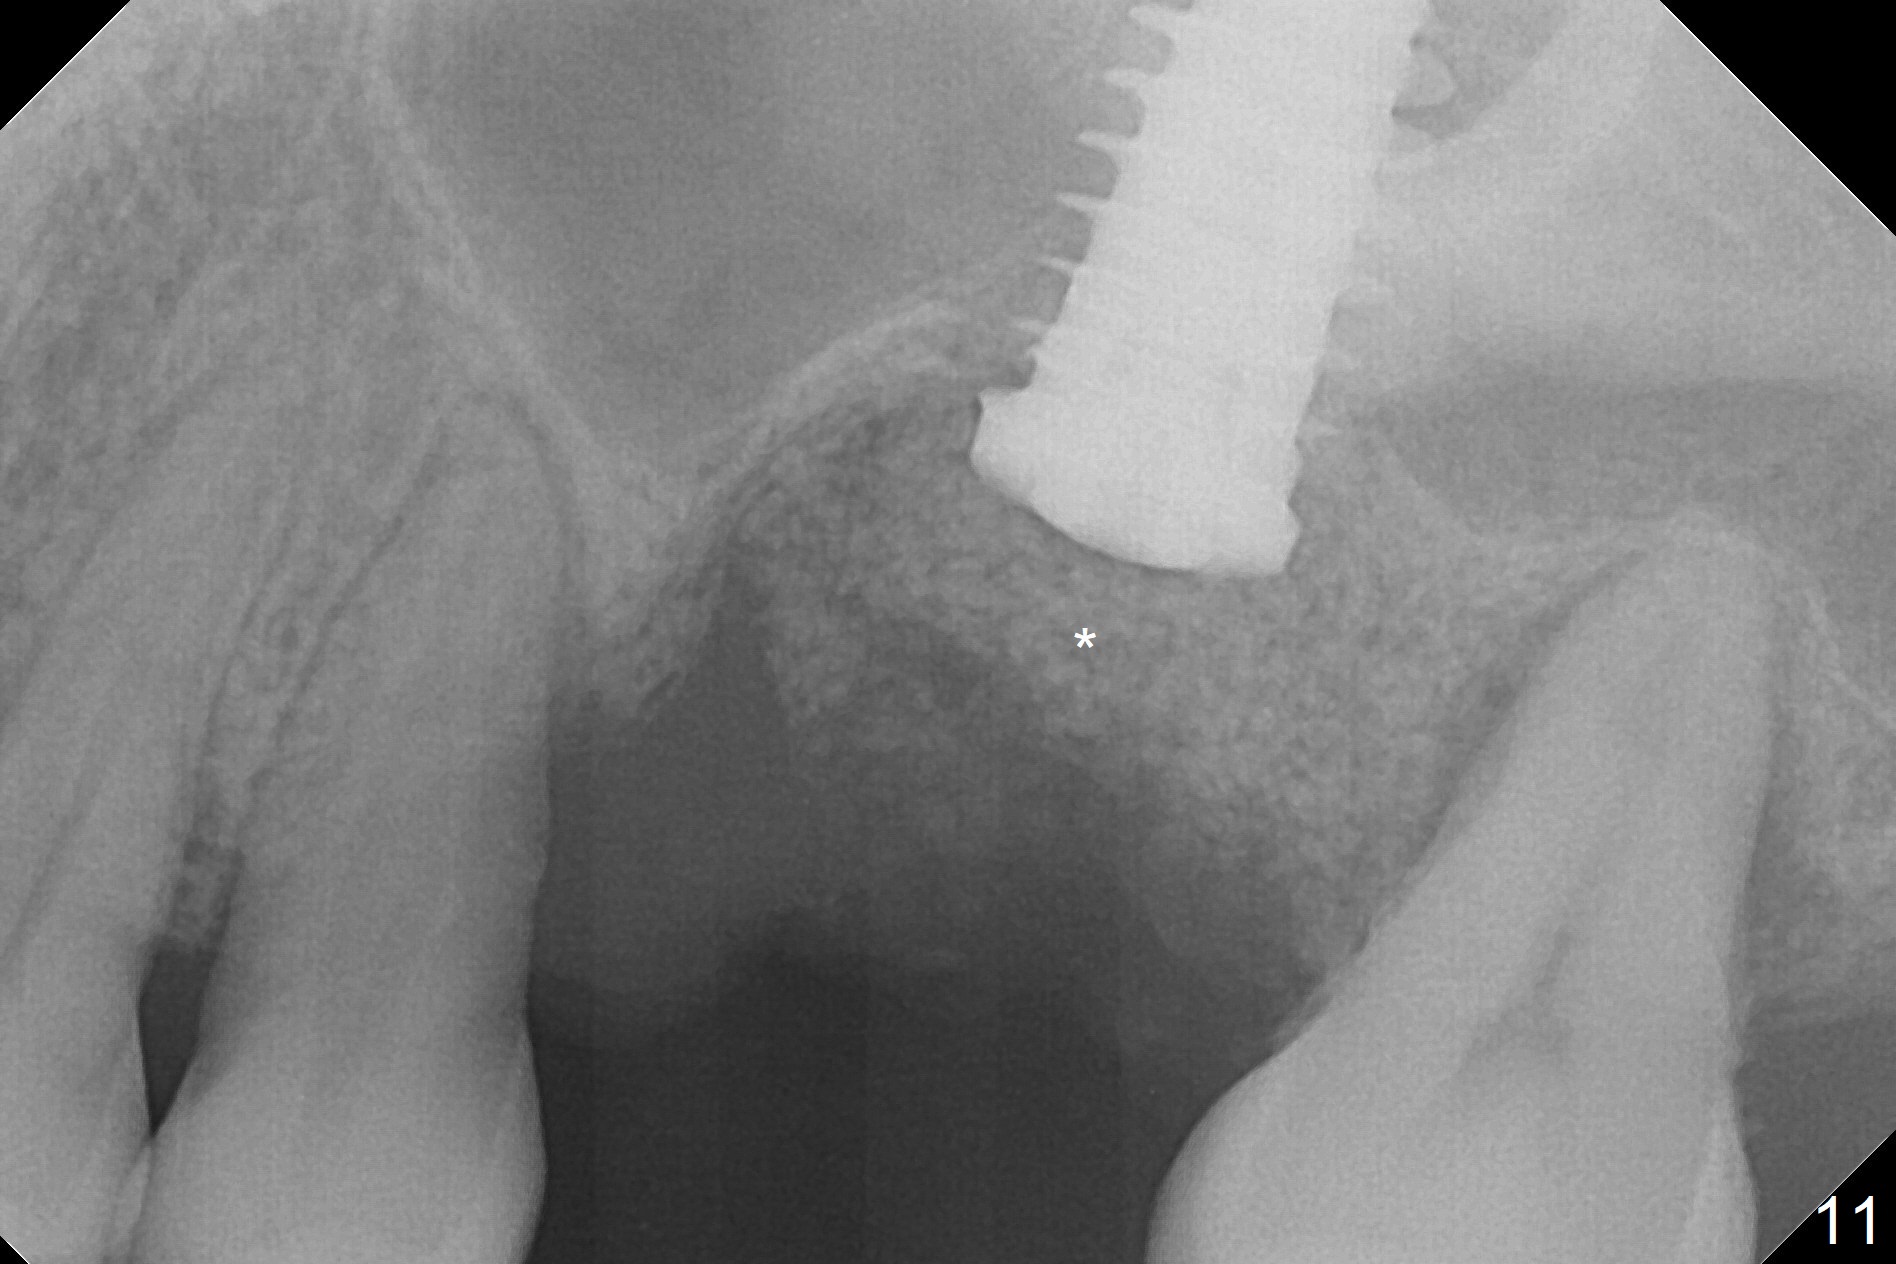

When the displaced tooth #14 (Fig.1) with palatal gingival recession (Fig.2) is extracted, the buccal plate is low, while the palatal one is lost.  Osteotomy is initiated in the bottom of the large socket with Marking Drill.  The bone turns bluish, suggesting thin bone (in fact less than 1 mm as well as low density).  Magic Sinus Lifter (Fig.3 *, Fig.4 blue area) is used for sinus lift (Fig.4 (red curved line: lifted sinus membrane; grey area: a portion of the lifted sinus floor), followed by insertion of a piece of PRF plug and Vanilla bone graft for sinus lift.  The osteotomy is enlarged lightly with 4.8 mm Magic Drill (compare black strips between Fig.4,5).  A 5x9 mm dummy implant (Fig.5 green) is dislodged into the sinus.  The lifted sinus membrane holds the implant in place.  The black thin strip in Fig.5 and black circle in Fig.6a (occlusal view) represents the osteotomy.  After increase in the osteotomy with Lindamann bur (Fig.6b red circle), the implant (Fig.6c green) is retrieved with endodontic forceps (Fig.6c two blue dots (beaks of the forceps); Fig.7,8).  With the enlarged osteotomy (Fig.6d), a 6x9 mm dummy implant is placed deep (Fig.9).  The definitive implant is 6.5x11 mm with insertion torque ~ 15 Ncm (Fig.10).  With placement of a healing screw and further placement of allograft (Fig.11 *), the socket is closed with PRF membrane and collagen plug (Fig.12).

Poor visibility for immediate implant in the molar region is another contributing factor for the dislodgement.  The patient returns for follow up 15 days (Fig.15) and 1 month (Fig.16) postop.  Bone graft seems to be stable around the implant.  The socket heals 4 months postop (Fig.20).  The implant seems to have been osteointegrated (Fig.17,18).  It will be backed up for ~ 3 mm to improve implant/crown ratio (Fig.19, as compared to Fig.14).  If it cannot be done, take impression immediately and make a subgingival provisional before suturing.